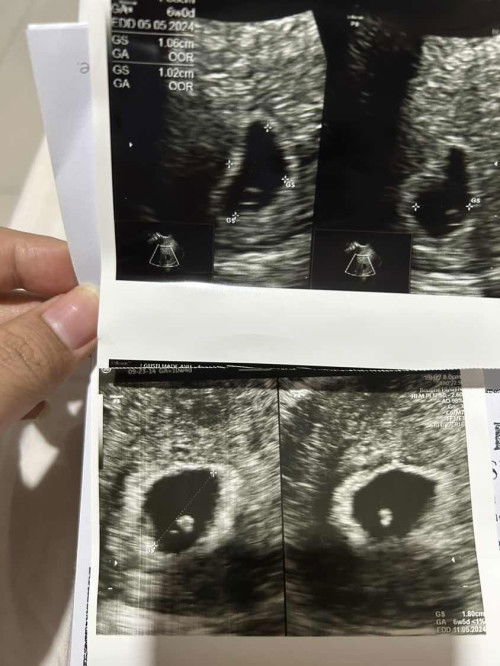

Hi moms.. saya habis usg 8 weeks dg kondisi terkadang perut kanan sakit dan kadang nge flek tp tidak banyak. Kata dokter janin nya belum terlihat, baru terlihat bulat kecil namun belum bisa dikatakan janin, ada yg punya pengalaman yg sama atau tau kondisi ini? Foto diatas usg 2 minggu yg lalu usia hampir 6 minggu, foto bawah usg hari ini usia +-8 minggu. Dokter bilang observasi sampai minggu depan jika tidak berkembang akan diambil tindakan. Minta doanya ya moms semoga janin saya tumbuh minggu depan.. #pleasehelp #firstmom #firstbaby #ingintahu